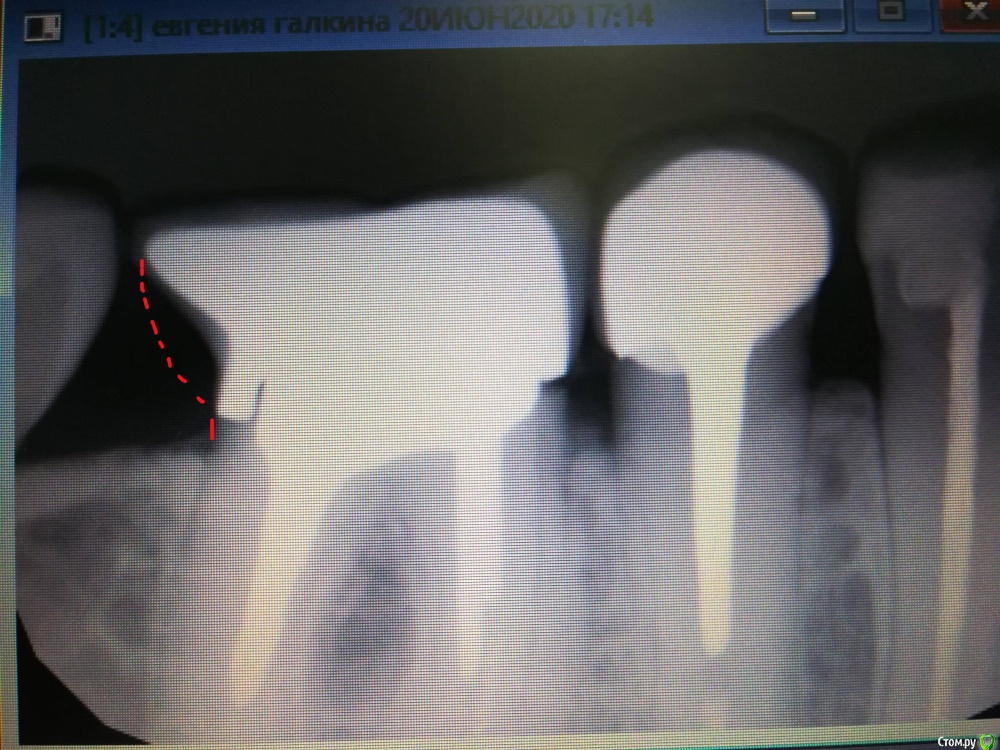

Evangeline Опубликовано 20 июня, 2020 Автор Поделиться Опубликовано 20 июня, 2020 Снимок 6 зуба. Ссылка на комментарий

chervoncevdaniil Опубликовано 24 июня, 2020 Поделиться Опубликовано 24 июня, 2020 Вы если возьметесь за коронку пальцами и попробуете ее подвигать вверх вниз,она поднимается и опускается или нет?Потому что одиночная коронка сама по себе двигаться не может,она просто свалится,тут вариант расцементировки вкладки,если все таки она действительно двигается,но из за того,что она многокорневая,она не выпадает,ее "ножки"в разных каналах не дают это сделать.В случае если дело в этом,то я боюсь вам уже это не решить,разборную культевую вкладку достать из зуба при этом чтобы от зуба что то осталось практически нереально,но в целом очень странно,потому что стоит она по снимку капитально и впринципе не должна была так быстро расцементироваться 1 Ссылка на комментарий